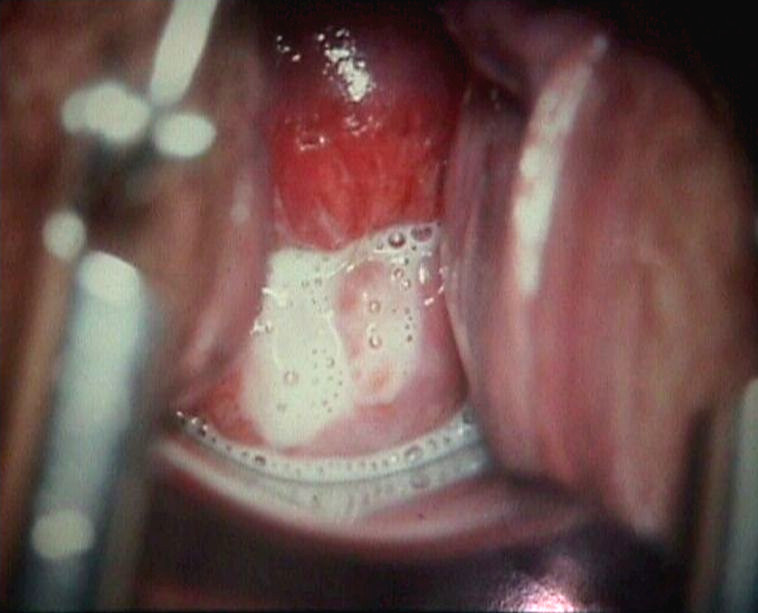

![Trichomonas vaginalis, trichomoniasis (click on photo to enlarge) [source: isis325 - Wikimedia - Creative Commons License 2.0] Trichomonas vaginalis, trichomoniasis](../../images/soa/trichomonas-vaginalis-1z.jpg) |

| foamy fluorine |

Trichomonas vaginalis |

Photos: Texas Tech University Health Sciences Center and isis325 - Wikimedia (Creative Commons License 2.0 ).